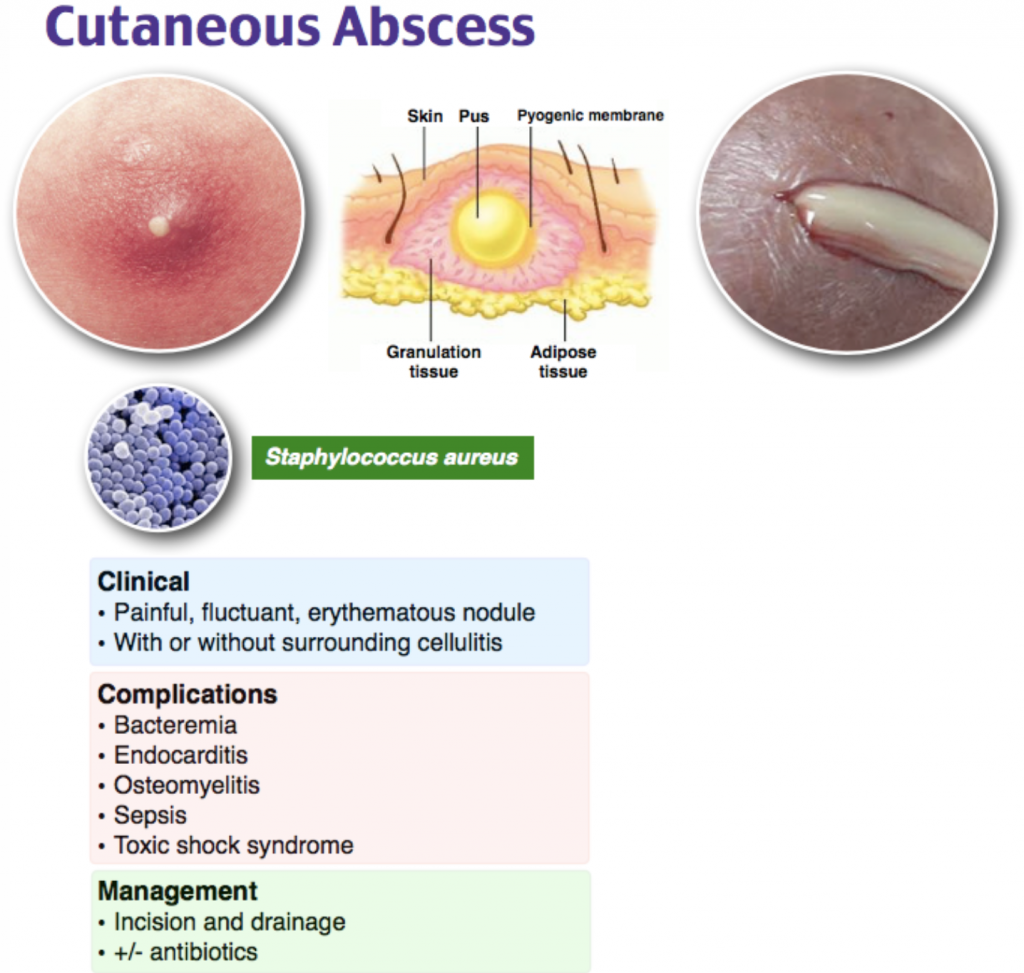

It’s usually caused by an infection and produces pus Phlegmon is an area of soft tissue or fluid density effacing or displacing usual fat or other connective tissue and shows variable enhancement However, an abscess typically has a. A phlegmon is a localized area of acute inflammation of the soft tissues

A phlegmon results when an acute infection is not confined as in the case of abscess

Instead the infection spreads along tissue planes and between muscle fibers. Phlegmon is a serious skin infection that affects the soft tissues, leading to inflammation and a collection of pus It is often caused by bacteria entering the skin through a. This article explores the causes, symptoms, diagnosis, and treatment of phlegmon, including its classifications based on clinical course, severity, location, cause, pathogenesis,.